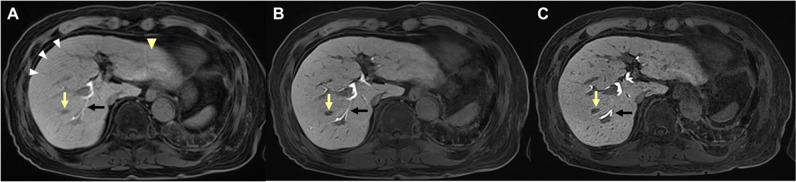

To investigate whether a deep learning (DL) controlled aliasing in parallel imaging results in higher acceleration (CAIPIRINHA)-volumetric interpolated breath-hold examination (VIBE) technique can improve image quality, lesion conspicuity, and lesion detection compared to a standard CAIPIRINHA-VIBE technique in gadoxetic acid-enhanced liver MRI.

This retrospective single-center study included 168 patients who underwent gadoxetic acid-enhanced liver MRI at 3 T using both standard CAIPIRINHA-VIBE and DL CAIPIRINHA-VIBE techniques on pre-contrast and hepatobiliary phase (HBP) images. Additionally, high-resolution (HR) DL CAIPIRINHA-VIBE was obtained with 1-mm slice thickness on the HBP. Three abdominal radiologists independently assessed the image quality and lesion conspicuity of pre-contrast and HBP images. Statistical analyses involved the Wilcoxon signed-rank test for image quality assessment and the generalized estimation equation for lesion conspicuity and detection evaluation.

DL and HR-DL CAIPIRINHA-VIBE demonstrated significantly improved overall image quality and reduced artifacts on pre-contrast and HBP images compared to standard CAIPIRINHA-VIBE (p < 0.001), with a shorter acquisition time (DL vs standard, 11 s vs 17 s). However, the former presented a more synthetic appearance (both p < 0.05). HR-DL CAIPIRINHA-VIBE showed superior lesion conspicuity to standard and DL CAIPIRINHA-VIBE on HBP images (p < 0.001). Moreover, HR-DL CAIPIRINHA-VIBE exhibited a significantly higher detection rate of small (< 2 cm) solid focal liver lesions (FLLs) on HBP images compared to standard CAIPIRINHA-VIBE (92.5% vs 87.4%; odds ratio = 1.83; p = 0.036).

DL and HR-DL CAIPIRINHA-VIBE achieved superior image quality compared to standard CAIPIRINHA-VIBE. Additionally, HR-DL CAIPIRINHA-VIBE improved the lesion conspicuity and detection of small solid FLLs. DL and HR-DL CAIPIRINHA-VIBE hold the potential clinical utility for gadoxetic acid-enhanced liver MRI.

与标准 CAIPIRINHA-VIBE 相比,DL 和 HR-DL CAIPIRINHA-VIBE 在平扫和 HBP 图像上均显著提高了整体图像质量,减少了伪影(p<0.001),同时采集时间更短(DL 比标准,11s 比 17s)。然而,前者的外观更具合成感(均 p<0.05)。在 HBP 图像上,HR-DL CAIPIRINHA-VIBE 比标准和 DL CAIPIRINHA-VIBE 具有更高的病灶显著性(p<0.001)。此外,在 HBP 图像上,HR-DL CAIPIRINHA-VIBE 检测到的小(<2cm)实性局灶性肝脏病变(FLL)的检出率显著高于标准 CAIPIRINHA-VIBE(92.5%比 87.4%;比值比=1.83;p=0.036)。

与标准 CAIPIRINHA-VIBE 相比,DL 和 HR-DL CAIPIRINHA-VIBE 获得了更好的图像质量。此外,HR-DL CAIPIRINHA-VIBE 提高了小的实性 FLL 的病灶显著性和检出率。DL 和 HR-DL CAIPIRINHA-VIBE 在钆塞酸增强肝脏 MRI 中具有潜在的临床应用价值。